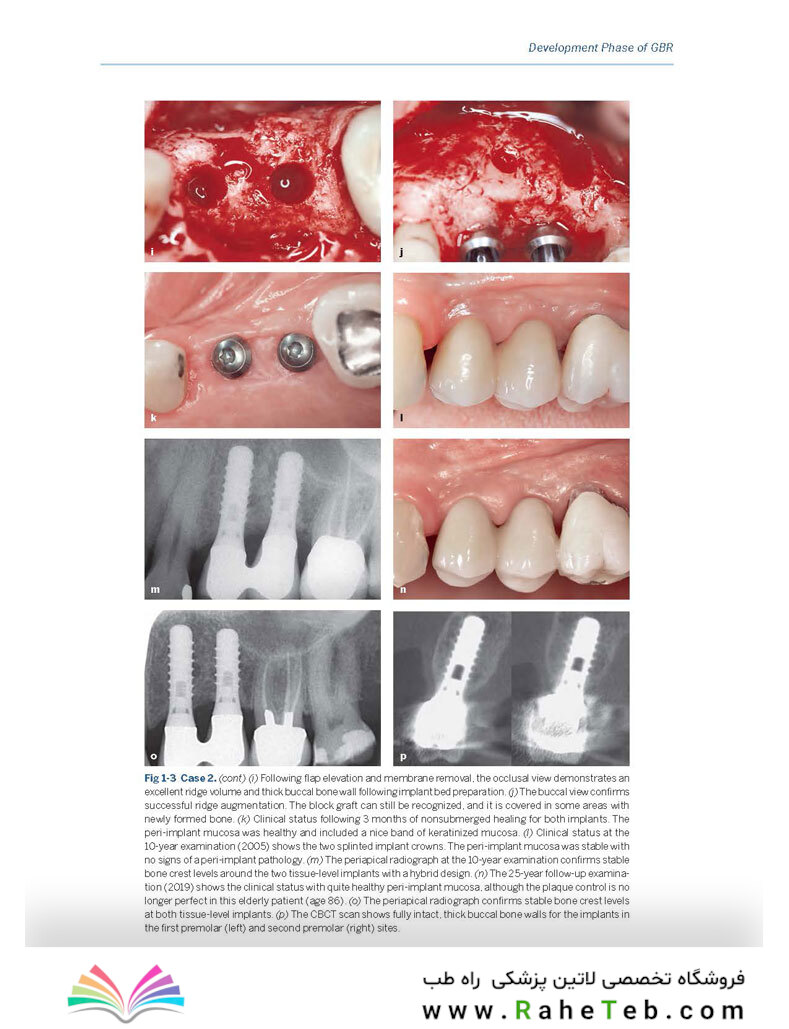

اما نقطه اوج این کتاب در بخش سوم آن نهفته است. در این بخش، یک طبقه بندی جدید و نوآورانه از نقایص استخوانی با نام "GBR Master" معرفی میشود که یک رویکرد سیستماتیک برای درمان انواع نقایص استخوانی ارائه میدهد. این رویکرد به شما کمک میکند تا با اطمینان و دقت بیشتری، پیچیده ترین موارد بالینی را مدیریت کنید. کتاب 30Years of Guided Bone Regeneration با تصاویر رنگی متعدد و گزارش های موردی غنی شده است تا مفاهیم تئوری را به بهترین شکل در عمل نشان دهد.